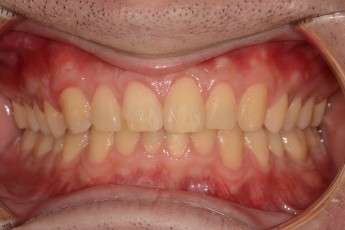

BEFORE & AFTER